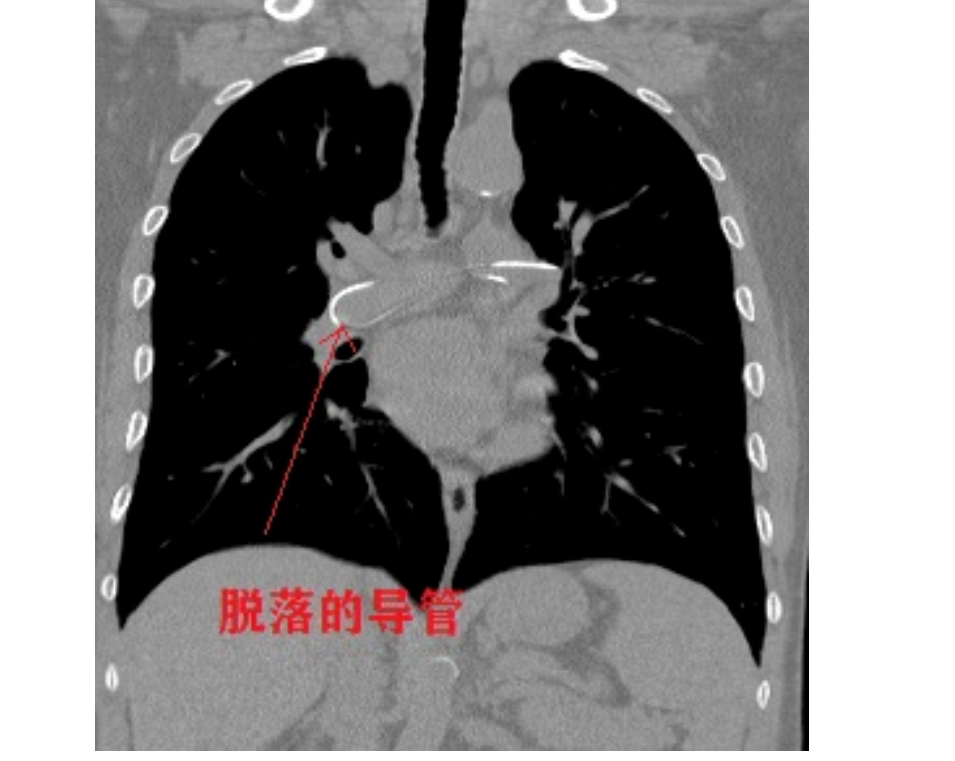

一名来自贵州施秉的59岁男性患者,4个月前因患白血病开始行PICC置管输液化疗,且长期于外院进行化疗及导管护理。近期该名患者到黔南州人民医院进行化疗,常规行胸部CT检查偶然发现其PICC导管出现断离并顺血流游走,经过心脏后卡在了肺动脉内。其一端在左上肺动脉,另一端在左下肺动脉,其余部分盘绕于肺动脉主干内。